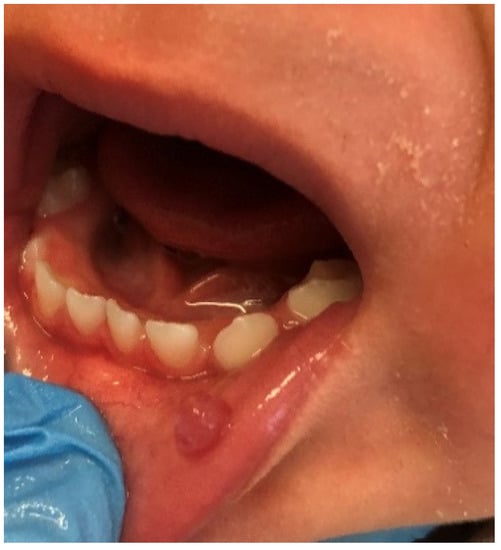

Mucoceles are a common alteration of minor salivary glands due to trauma followed by obstruction of the salivary gland duct which effects cystic swelling, as seen in Figure 4 [22]. In this study they were diagnosed as the second most prevalent OML among the entire group of subjects (10.5%) among girls and school-age children. A similar incidence (13.5%) was revealed by Sousa et al. [23]. It was also the third most common lesion in adolescents, and one of the least frequent among preschool children (only two cases). This is not surprising, since many studies show that such disorders are often observed in the second decade of life and rarely in infants [24,25]. In our research, this pathology was more frequent among girls than boys, similar to observations made by Vale et al. [26]. In the same study, a histological revision of 315 diagnoses of pediatric patients revealed a very high incidence of mucocele, amounting to 33.3%. Other analyses by Wang et al. [27] and Lima et al. [18] also showed a high frequency of mucoceles, 24.5% and 17.2%, respectively. On the other hand, there are also other reports showing a lower prevalence of mucoceles in the pediatric population, but even in these studies with a lower incidence, mucoceles were always among the most commonly diagnosed OMLs [1,2,3,10,20,28,29,30].

Figure 4.

Mucocele on the lower lip of an adolescent girl. Typical dome-shaped fluctuant mucosal swelling. The lower lip is the most common site for this lesion to develop due to the relative ease of traumatizing this area.